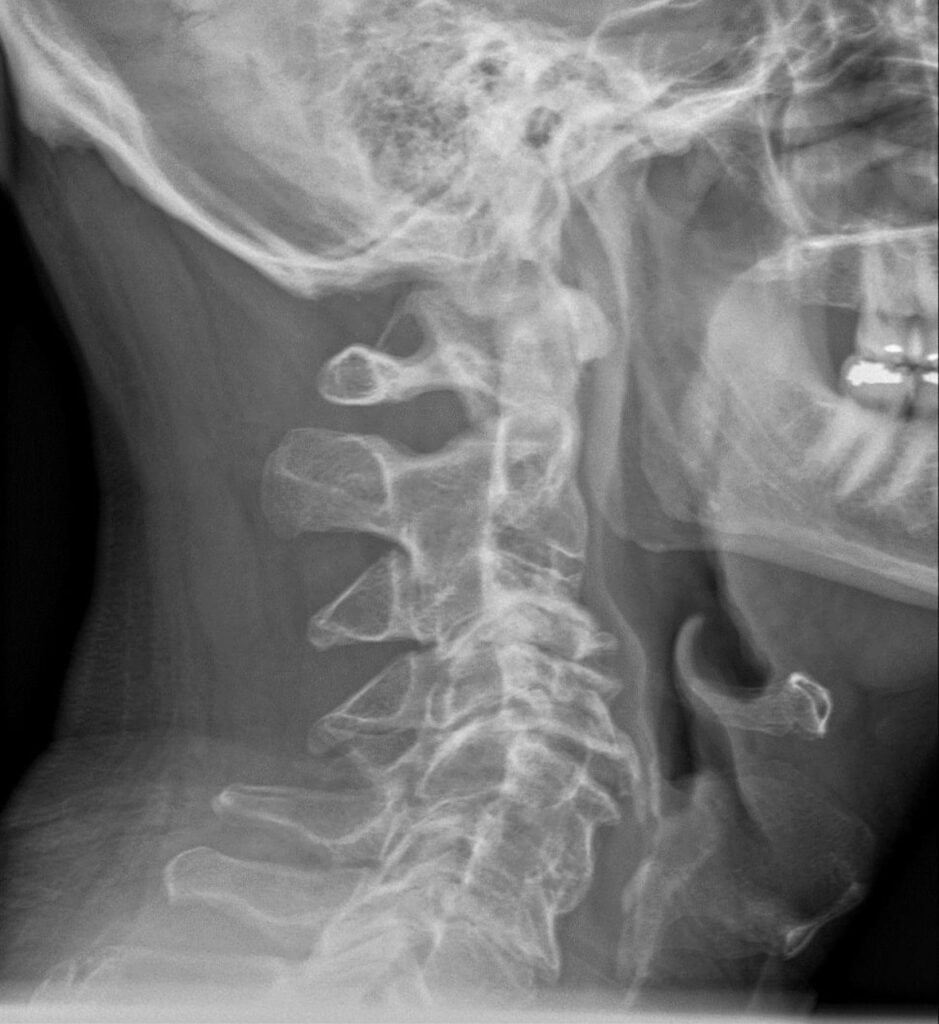

Men så är det inte för väldigt många. Många går runt med detta i flera år, och efter x antal rehabövningar, injektioner och i värsta fall operationer träffar jag dem och tänker, ”ok, varför läker inte detta då?”. Svaret är, som bilden över kanska hintar till, att många axelbesvär är sekundära tillstånd till ändrade biomekaniska förhållanden. Framför allt i nacken. Jag har till godo att träffa en patient med axelbesvär som inte har ett problem i nacken. Nackproblem i kombination med systemisk inflammation och metabola rubbningar verkar vara katastrof för axelns hälsa. Så för att upprepa den stora bilden igen. Vi måste adressera hela systemet. Reducera fysisk, kemisk och emotionell stress. Nackproblem måste lösas, och vi behöver sömn och näringsämnen.